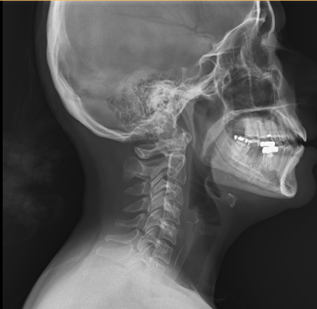

Case Overview A 45-year-old woman arrived at our Emergency Department experiencing severe throat pain shortly after accidentally swallowing a fish bone during dinner. She reported intense difficulty swallowing, even her own saliva, and pain radiating to her neck. On examination, her pulse was elevated at 110 beats per minute, and her neck was extremely tender to the touch.

A rapid X-ray confirmed the presence of a fish bone lodged in the upper esophagus—a potentially dangerous situation if not addressed quickly.